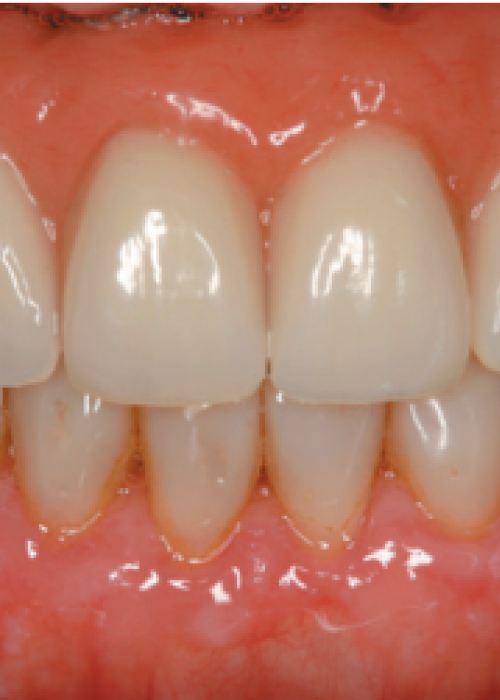

Resolución de un caso con implicación estética en el sector antero-superior. A propósito de un caso